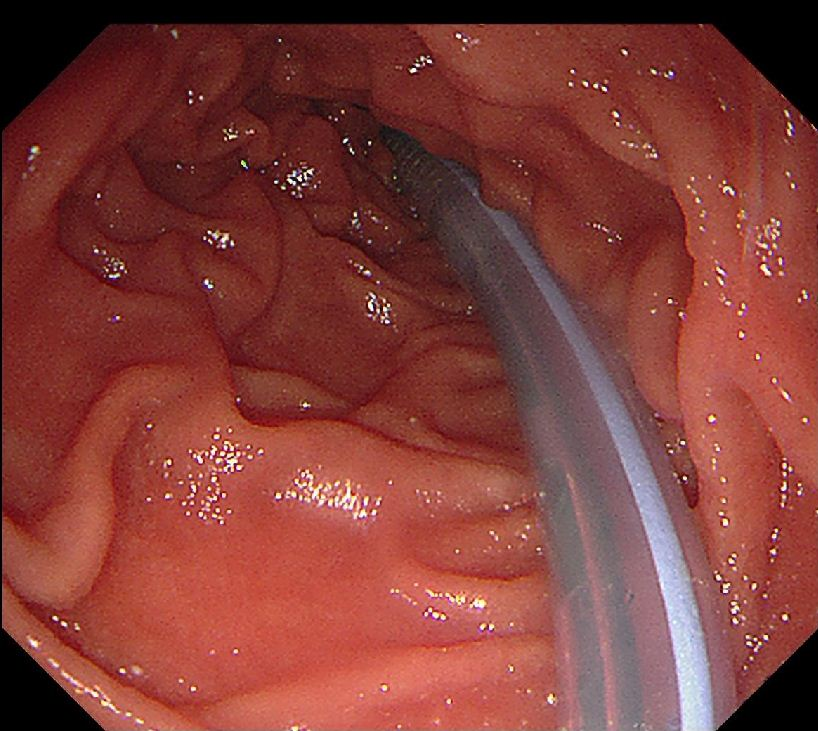

消化内科主治医师李浩然和微创中(第二手术区)心护士长刘骥为患者行内镜下食管内异物取出术。术中可见一枣核卡顿于食管入口处,周围黏膜充血水肿伴破溃。使用异物钳钳取枣核头端,拖入透明膜内与内镜共同退出。二次进镜,食管入口处黏膜可见血肿、破溃及少量渗血,并行内镜下空肠营养管置管术。

空肠营养管置管